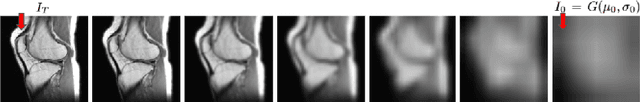

Abstract:Medical image denoising is essential for improving the reliability of clinical diagnosis and guiding subsequent image-based tasks. In this paper, we propose a multi-scale approach that integrates anisotropic Gaussian filtering with progressive Bezier-path redrawing. Our method constructs a scale-space pyramid to mitigate noise while preserving critical structural details. Starting at the coarsest scale, we segment partially denoised images into coherent components and redraw each using a parametric Bezier path with representative color. Through iterative refinements at finer scales, small and intricate structures are accurately reconstructed, while large homogeneous regions remain robustly smoothed. We employ both mean square error and self-intersection constraints to maintain shape coherence during path optimization. Empirical results on multiple MRI datasets demonstrate consistent improvements in PSNR and SSIM over competing methods. This coarse-to-fine framework offers a robust, data-efficient solution for cross-domain denoising, reinforcing its potential clinical utility and versatility. Future work extends this technique to three-dimensional data.